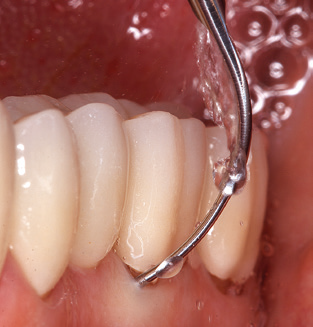

Fig. 4: Flexible probes with millimetre markings are recommended for the probing of dental implants (e.g. Colorvue Kit PCV11KIT6, Hu­Friedy). – Fig. 5a and b: A straight working tip (1P, W&H Dentalwerk Bürmoos GmbH) is a suitable instrument for use on all natural teeth. – Fig. 6: Curved working tips (3Pr/3Pl, W&H Dentalwerk Bürmoos GmbH) lend themselves to the processing of difficult-to-reach areas of the tooth and root surfaces (e.g. furcations). – Fig. 7: The tapered, hexagonal implant cleaning tip (1I, W&H Dentalwerk Bürmoos GmbH) permits atraumatic and efficient cleaning of the crown and abutment surfaces. – Fig. 8: Titanium and carbon curettes are suitable instruments for the manual cleaning of the implant surfaces.

Good illumination of the working field facilitates the process considerably. The system used by the authors achieves this thanks to a 5x LED ring integrated in the handpiece. Naturally, a range of working tips for different indications is also offered. A straight, universally employable tip is the basic instrument required for machine cleaning of natural teeth (Fig. 5a and b). Curved tips, which allow access to exposed furcations, are also available for hard-to-reach areas in the posterior region (Fig. 6).